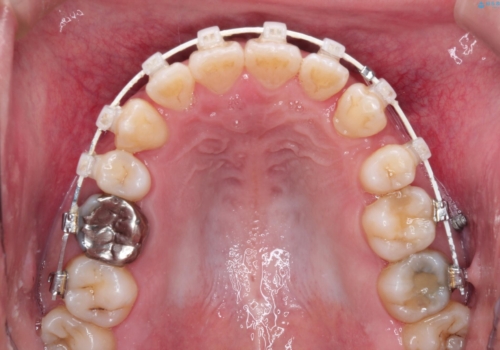

- 審美装置(ブラケット:白/ワイヤー:白)

- 2年3ヶ月

初診時の歯並びの状態としては、右上の犬歯がいわゆる八重歯の状態であり、強いガタガタが上下ともにある状態でした。

スペースの不足量が多く、抜歯を伴うワイヤー矯正にて治療を行いました。

若干の口元の突出感もあったため、抜歯によるスペースを利用し、がたつきの改善と前歯の後退をを行いました。